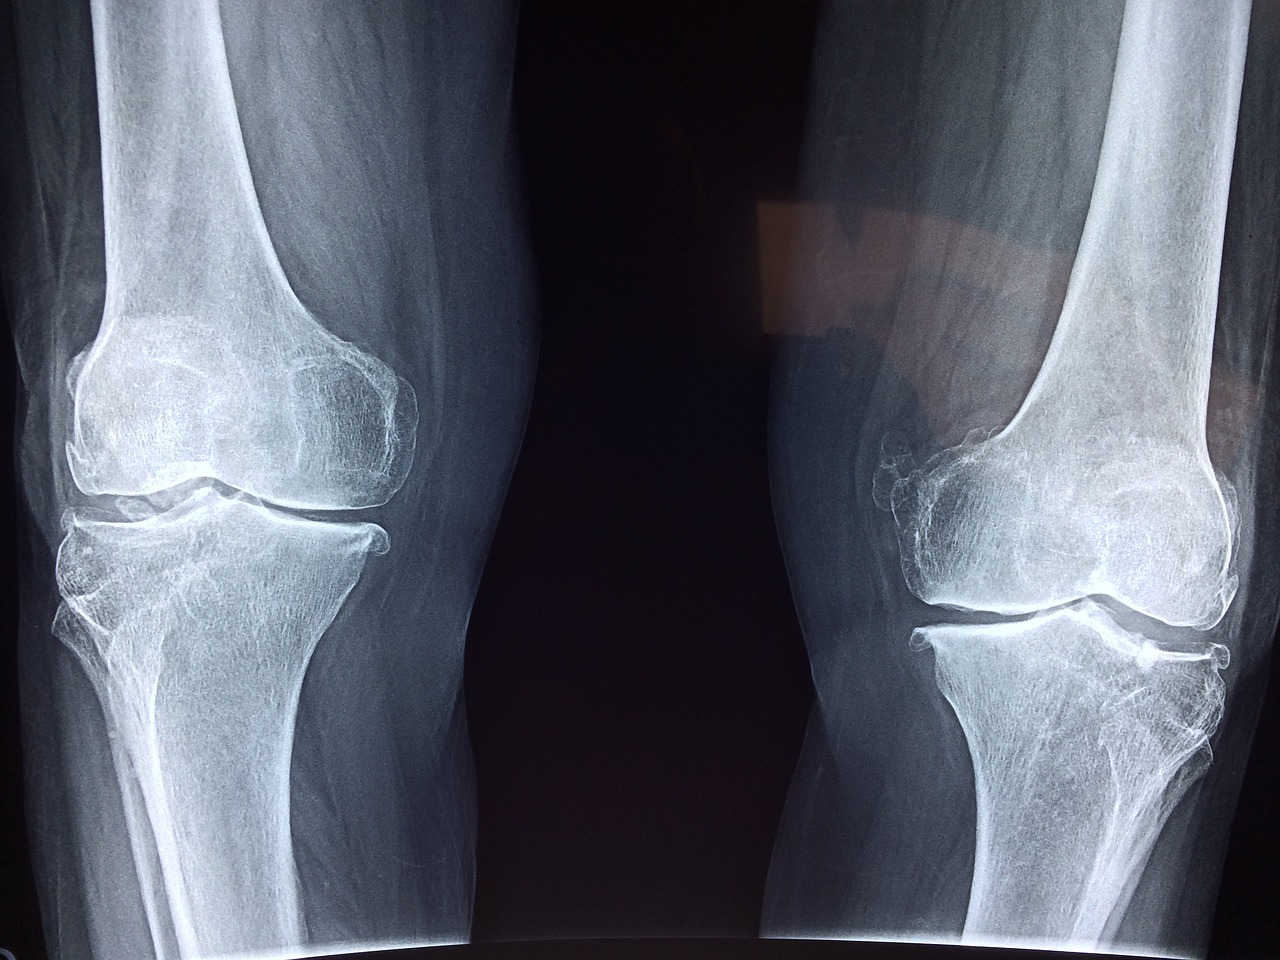

퇴행성 관절염은 우리가 일상생활에서 자주 겪는 질병 중 하나입니다. 관절의 기능을 제대로 수행하지 못하게 만들며, 심한 경우에는 통증과 장애를 유발할 수 있습니다. 퇴행성 관절염은 다양한 관절에서 발생할 수 있습니다. 가장 흔한 형태는 슬개골 관절염이며, 무릎 관절의 연골이 손상되어 발생합니다. 또한 요추, 목, 손목, 손가락, 발목 등 다른 관절에서도 발병할 수 있습니다. 이는 관절의 사용 빈도와 부하에 따라 달라질 수 있습니다. 퇴행성 관절염의 주요 증상은 관절통증, 부종, 그리고 관절 운동의 제한입니다. 통증은 특히 관절을 사용하거나 앉아서 일어날 때 더 심해지는 경향이 있습니다. 부종은 염증 반응으로 인해 발생하며, 관절 주위의 부분이 붓는 것을 나타냅니다. 관절 운동의 제한은 연골 손상으로 인해 관절이 움직이기 어려워지는 것을 의미합니다. 퇴행성 관절염은 완치되지 않지만 증상을 완하하고 관리하는 데 도움이 되는 다양한 치료법이 있습니다. 약물치료, 물리치료, 운동 및 생활 방식의 변화 등이 그 예입니다. 또한 관절 보호를 위해 적절한 보조기구를 사용하는 것이 중요합니다. 이러한 치료와 관리를 통해 환자는 일상생활에서 더 나은 편안함을 누릴 수 있습니다. 퇴행성 관절염은 우리의 삶에 큰 영향을 미치는 질병입니다. 하지만 적절한 치료와 관리를 통해 증상을 완화하고 생활의 질을 향상할 수 있습니다. 더불어 예방에도 신경 써야 합니다. 건강한 식습관과 적절한 운동은 퇴행성 관절염의 발병을 예방하는 데 도움이 될 수 있습니다.